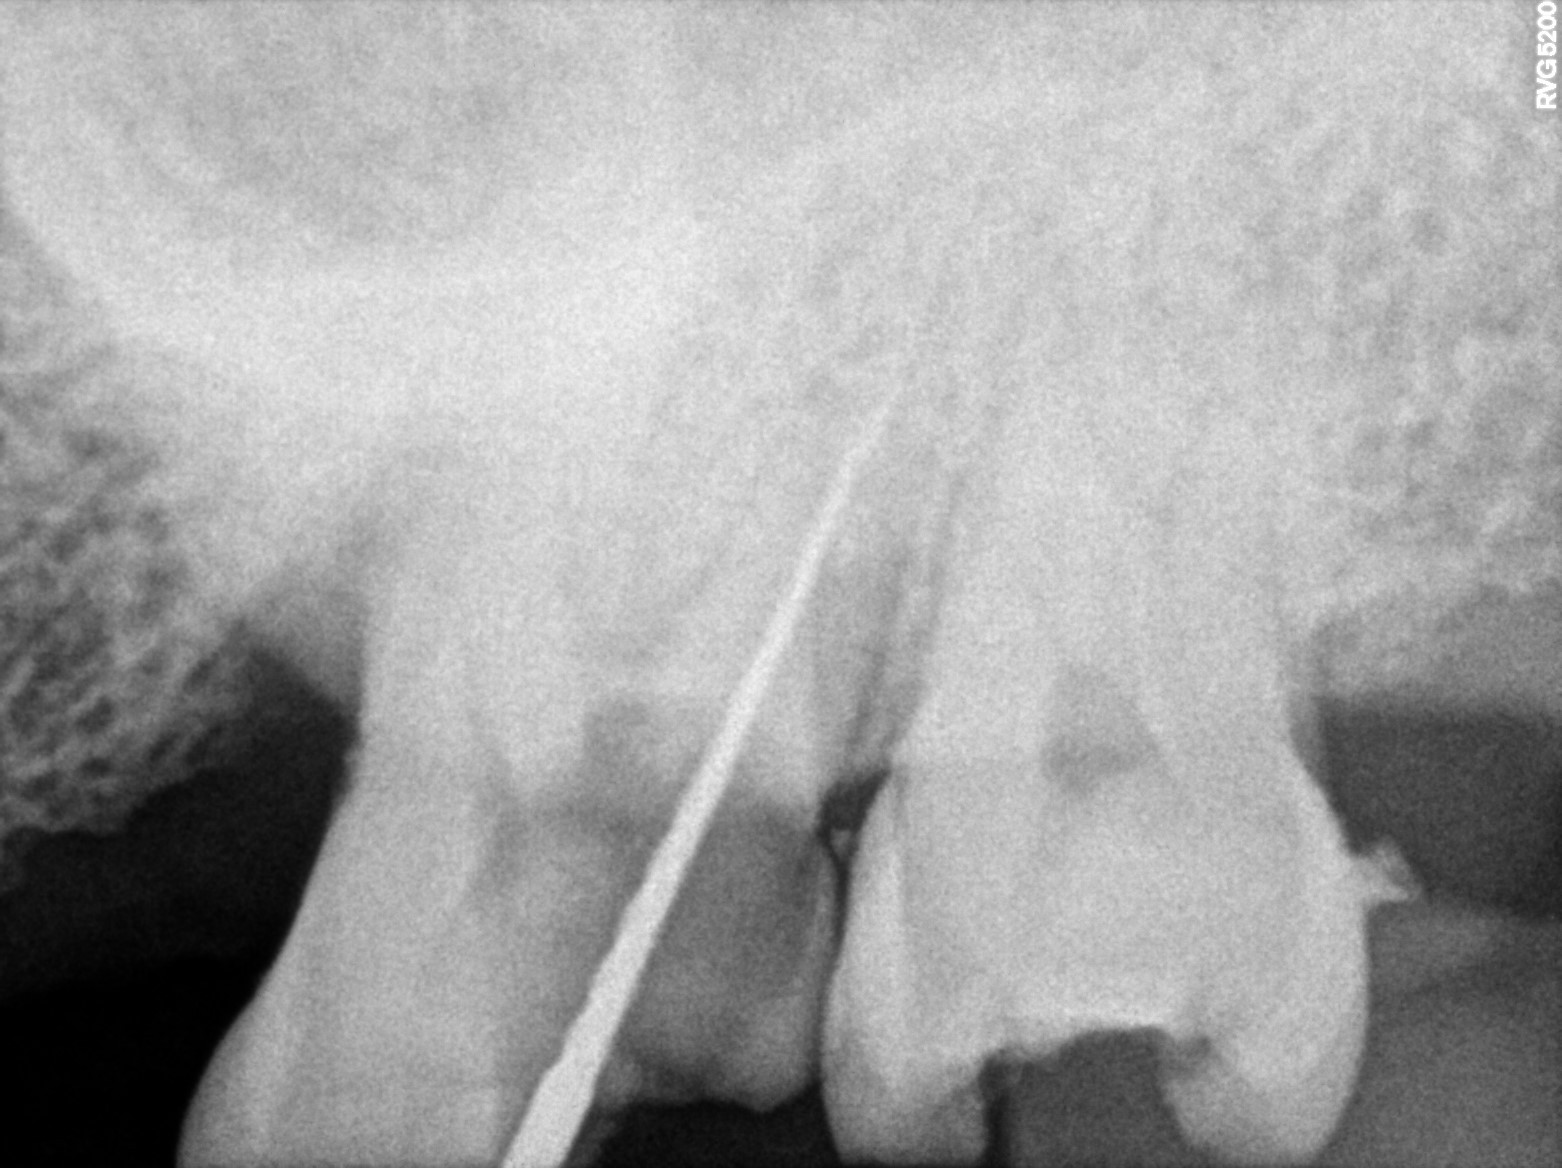

| Necrosis of dental pulp | K04.1 | 234946006 | resolved | 2026-03-17 | a/o with 27, bmp mb 0.5 stopper db 1 stopper palatal 2 stopper 20.06 all three canals |

| Root canal treatment | 234780006 | D3330 Endodontic therapy, molar tooth | ##27 | 2026-03-17 | completed | a/o with 27, bmp mb 0.5 stopper db 1 stopper palatal 2 stopper 20.06 all three canals |

| 2026-03-17 14:20 | fulfilled | a/o with 27, bmp mb 0.5 stopper db 1 stopper palatal 2 stopper 20.06 all three canals — Dr Riyaz |

Dental Radiographs FHIR: DocumentReference · LOINC 24641-7

xray_1773736525_0.jpg

24641-7